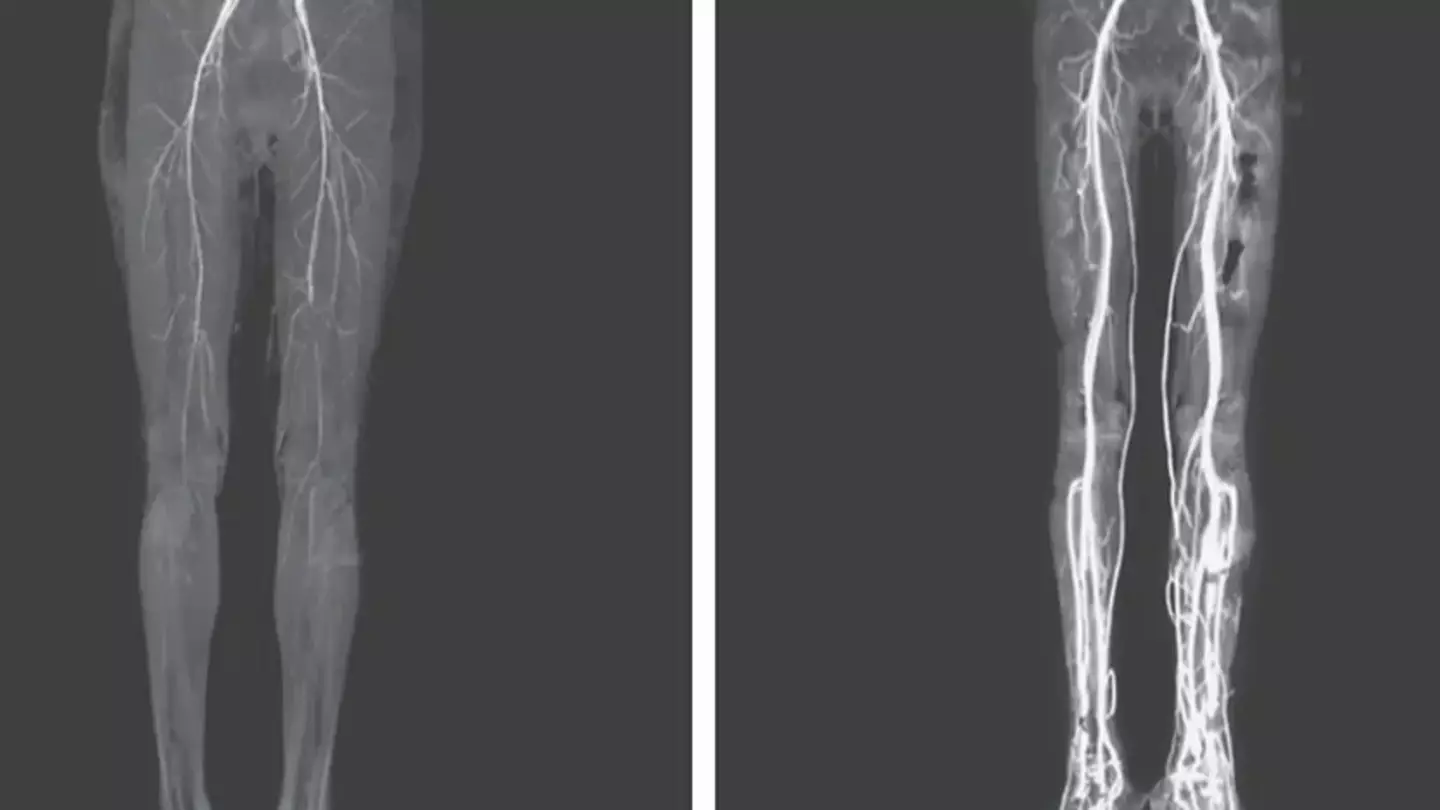

When doctors looked her over, they noticed how her feet had become discolored, while she was noticeably finding it difficult to walk. Upon further examination they realized her legs were cold - despite complaints that they were burning - and they couldn't find a pulse coming from the popliteal and dorsalis pedis arteries.

A CT (computed tomography) scan uncovered that her arteries had narrowed, and after a simple blood thinner drug was administered the pain was alleviated greatly, and her legs began to get warmer as the blood flowed through her legs.